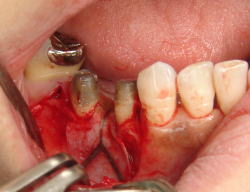

注:以下の外科処置に関する説明用写真は、歯肉を剝離したり、出血している写真もあります。

それらが不快に感じるかたは、ご覧にならないようお願いいたします。

骨のなくなっている所をあらかじめ、診断し、歯肉を切開しました

やはり、大きく骨が無くなっていました。

幼弱な骨様の組織ができていました。

この組織が、硬い骨になっていくのを待たねばなりませんが、成功しました。

歯ぐきを戻して、傷の治りを待ちます。